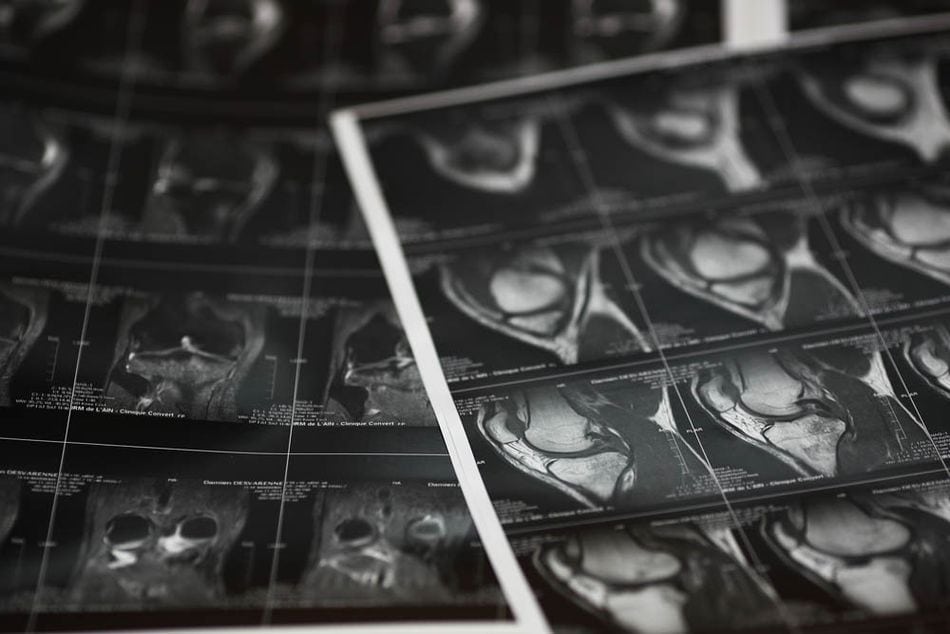

Annie a 62 ans, une gonarthrose (arthrose du genou) sévère, que les traitements médicamenteux ne peuvent plus soulager. Sa rhumatologue a fini d’injecter tout ce qu’elle pouvait dans son genou malade. Elle boîte et ne peut plus marcher sans douleurs. Elle vient à ma consultation pour discuter d’une mise en place d’une prothèse totale du genou.